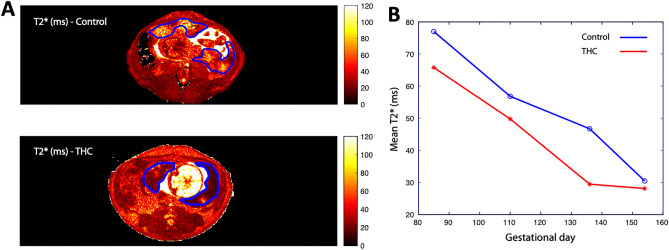

For more comprehensive quantification of blood flow across the entire placenta, DCE-MRI was utilized to assess maternal perfusion of the IVS. Total placental volumetric blood flow was found to be significantly lower (p < 0.05) at G135 and G155 in THC-exposed versus control animals in post hoc comparison (Table 3). Placental oxygen availability was assessed using BOLD-MRI through analysis of quantitative placental T2* values. In control placentas at four timepoints across pregnancy, MR image voxels proximal to spiral artery sources of oxygenated maternal blood are characterized by relatively long T2* (Fig. 3), as previously described35. Concentration of deoxyhemoglobin is higher, reflected by decreased T2*, further from the spiral arteries, secondary to fetal oxygen uptake. There was a statistically significant smaller fraction of large T2* values in THC-exposed animals compared to controls across pregnancy (p = 0.04), demonstrating decreased placental perfusion and fetal oxygen availability in the former (Fig. 3).